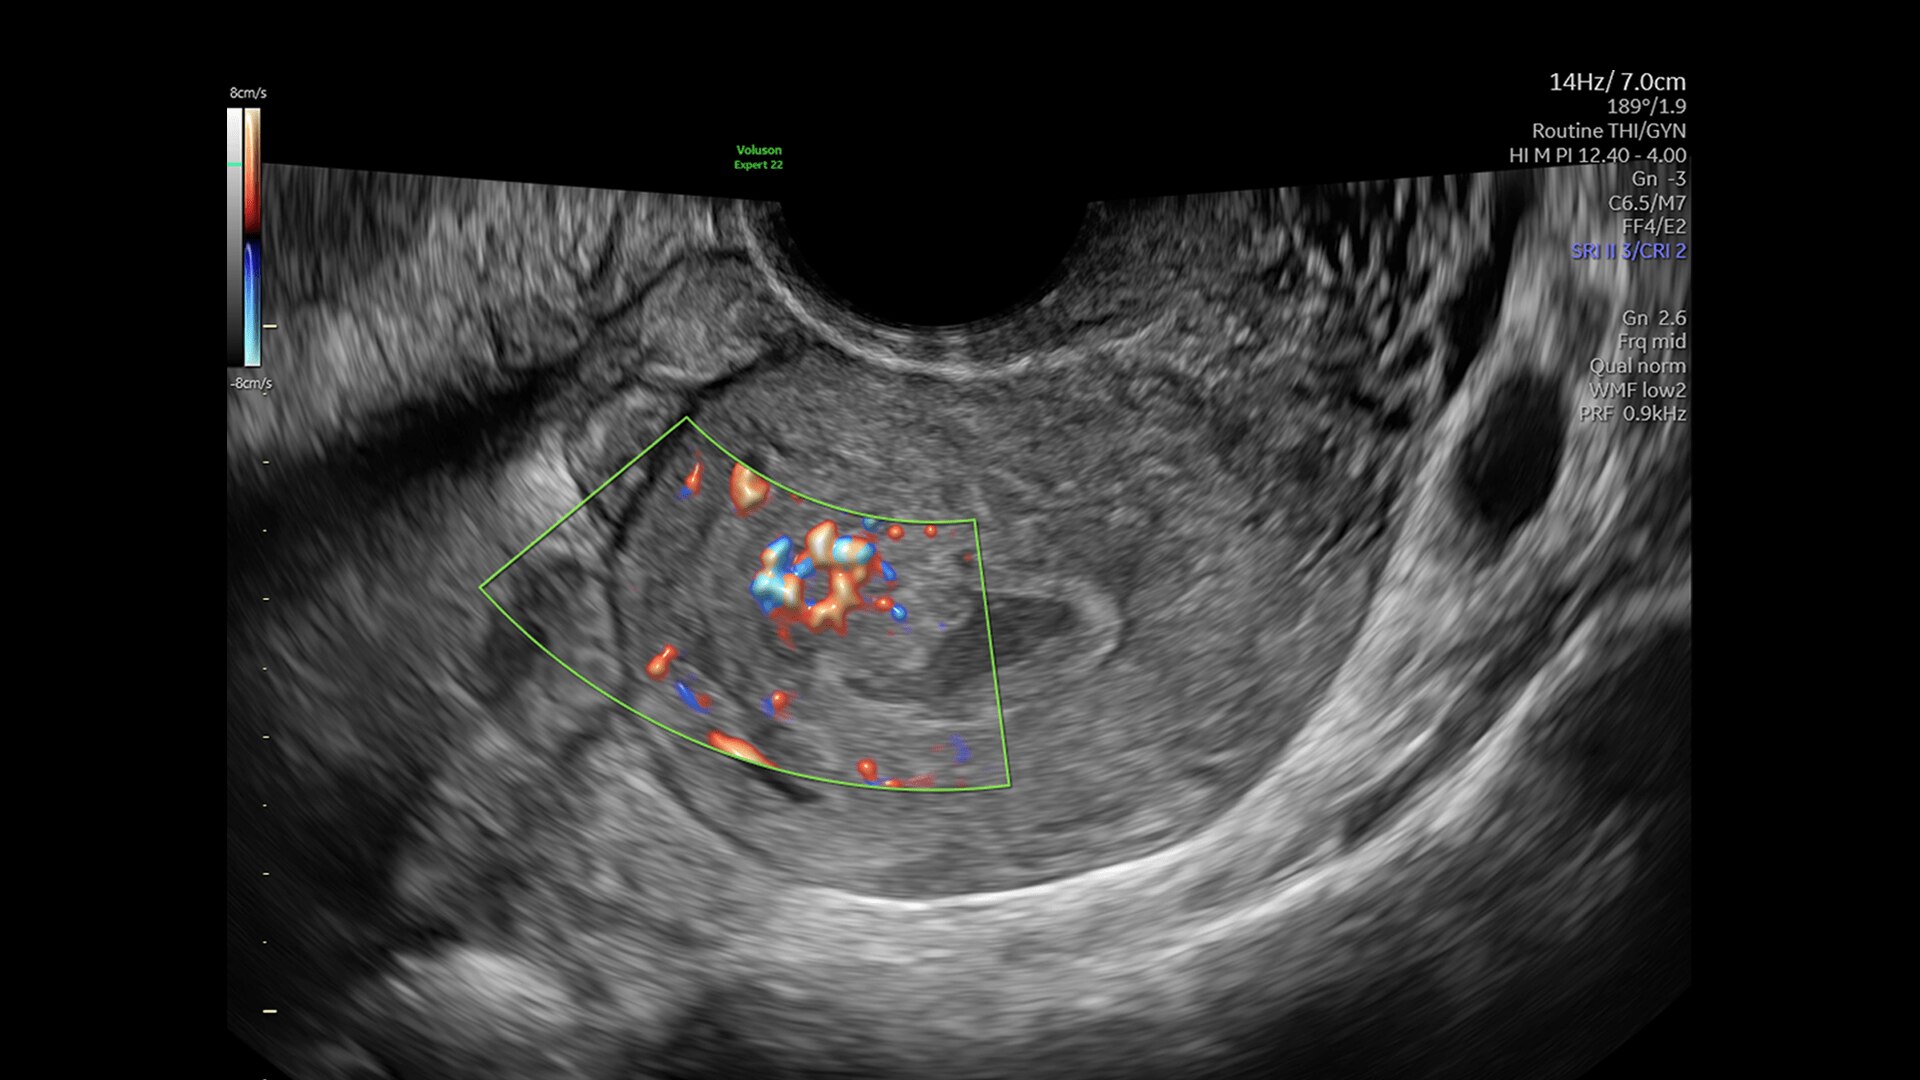

DOPPLER IMAGING

Beyond Basic Blood Flow

Voluson is pushing imaging boundaries to make blood flow assessment faster and easier. Our advanced technologies, including Graphic flow, Radiantflow, Slowflow, and Radiant imaging, increase resolution and sensitivity in color and pulsed wave Doppler for unprecedented clarity